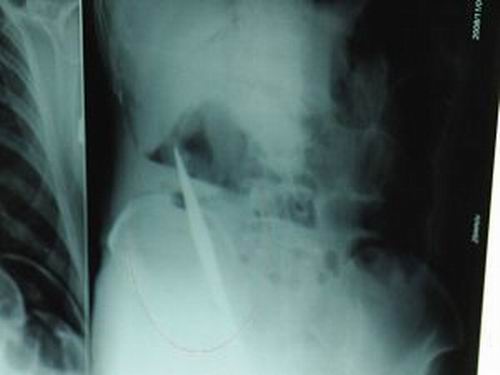

X光片上,尖刀清晰可見。

從男子體內(nèi)取出的尖刀足足有19厘米長(zhǎng)。

江蘇銅山一58歲男子因服毒被送到醫(yī)院搶救,可醫(yī)生采取搶救措施后卻發(fā)現(xiàn)效果不佳。后來經(jīng)細(xì)致檢查,醫(yī)生有了個(gè)驚人的發(fā)現(xiàn),該男子的體內(nèi)竟然有一把尖刀,醫(yī)生通過手術(shù)將位于其腹部右側(cè)橫結(jié)腸下緣的尖刀取了出來。這把尖刀足足有19厘米長(zhǎng)!據(jù)醫(yī)生推測(cè),這把刀應(yīng)該是從肛門推進(jìn)體內(nèi)的,不知男子為何想以如此殘酷的方式結(jié)束自己生命。由于搶救及時(shí),該男子已暫時(shí)脫離危險(xiǎn)。

昨天(11月6日)上午,記者在徐州礦務(wù)集團(tuán)總醫(yī)院重癥監(jiān)護(hù)室見到了這名男子,目前他雖然已經(jīng)恢復(fù)了意識(shí),但還不能開口說話,需要呼吸機(jī)輔助呼吸。據(jù)醫(yī)生介紹,4日中午12時(shí)左右,這名男子因服毒輕生被緊急送到醫(yī)院進(jìn)行搶救,之前,這名男子已經(jīng)在當(dāng)?shù)剜l(xiāng)鎮(zhèn)醫(yī)院進(jìn)行了近20小時(shí)的治療,但效果不佳!安∪吮晦D(zhuǎn)院到礦總院時(shí)已神志不清,血壓極低,處于休克狀態(tài)!本茸o(hù)人員給男子洗胃、初步處理以后,發(fā)現(xiàn)男子呼吸急促,于是趕緊給他拍片檢查。結(jié)果讓所有的醫(yī)生大吃一驚,竟有一把尖狀異物橫在該男子腹腔內(nèi)!當(dāng)天下午5時(shí)30分,輕生男子被推上了手術(shù)臺(tái)。經(jīng)過40多分鐘的手術(shù),該男子腹腔被打開,手術(shù)醫(yī)生發(fā)現(xiàn),男子體內(nèi)的金屬狀異物竟然是一把長(zhǎng)19厘米的尖刀!

醫(yī)生告訴記者,手術(shù)后,醫(yī)生在病人身上并未發(fā)現(xiàn)刀痕,最后,經(jīng)過檢查發(fā)現(xiàn),在該男子直腸處找到穿孔。醫(yī)生從醫(yī)學(xué)角度分析后認(rèn)為,這把尖刀應(yīng)該是從肛門插入直腸的。